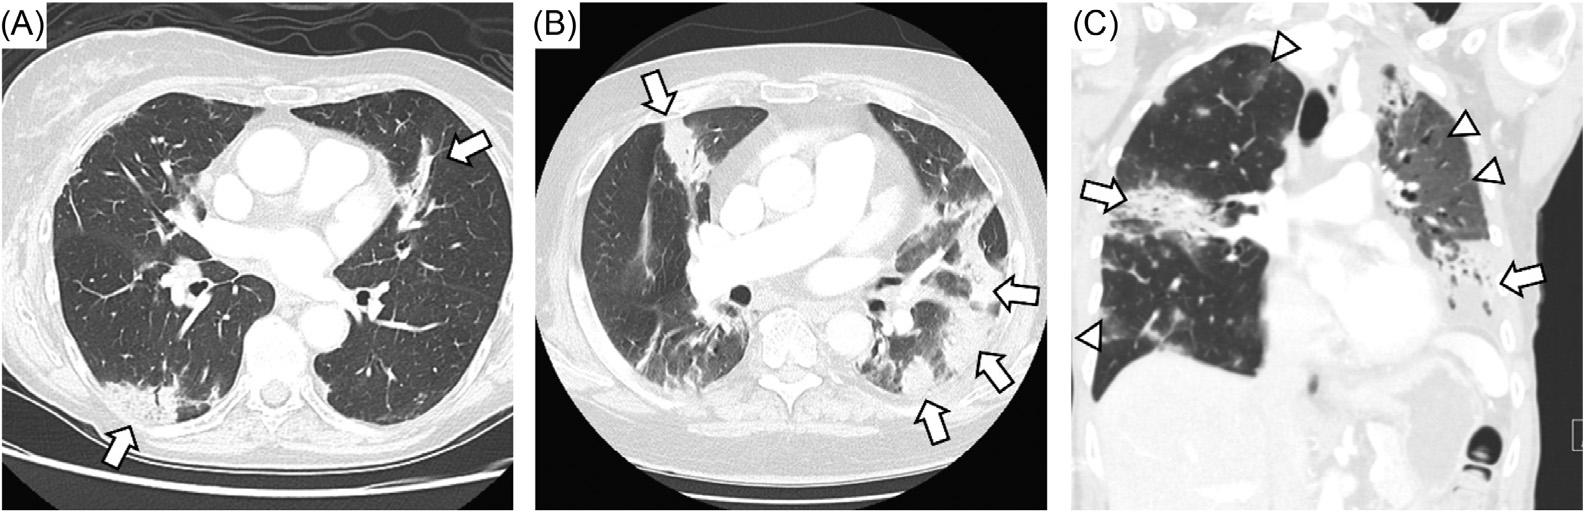

Brent King, MD, MMM University Texas, Houston

Christopher E. San Miguel, MD

Ohio State University Wexner Medical Center